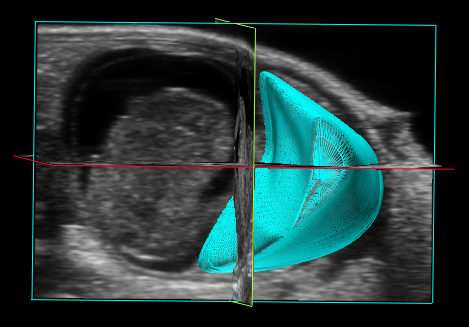

Heart - B Mode

3D Reconstitution

With the 3D Mode you will see the entire shape of your target anatomy on a micrometer scale. 3D Mode allows for measurements of area, height, length and volume of the target anatomy.

Aortic arc

Combining 3D Mode with Color Doppler, Power Doppler, Non-Linear Contrast Mode or Photoacoustics sub-modes makes it possible to extract even more parameters such as depth, volume and percent vascularity, all at a micrometer scale.